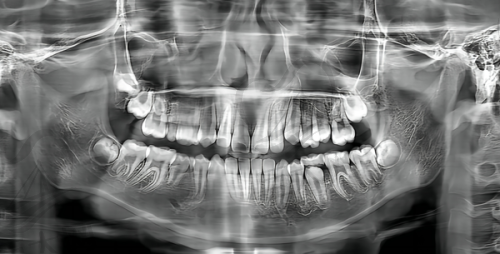

数字化种植牙是宣城大医口腔的特色项目之一。其中,数字化导板种植牙相比传统的种植牙有诸多优势。传统种植牙在手术过程中可能存在一定的不确定性,而数字化导板种植牙运用了数字导板技术植入植体。这种技术可以避开神经血管,增加了手术的成功几率和植体的存活能力。对于那些需要种植牙的患者来说,这无疑是一个更安心、更可靠的选择。想象一下,在进行种植牙手术时,能够精细地避开神经血管,大大降低手术风险,术后植体的存活能力也更高,这对于修复口腔功能和美观都有着重要的意义。